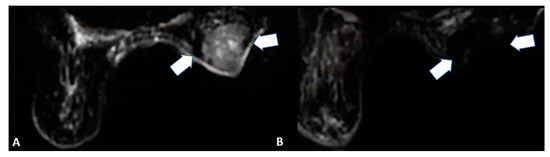

- Retromaxillary: In the case of a retromaxillary approach, the maxilla is used as a landmark. This approach is mostly used for lesions located in the masticatory space and the pharyngeal and laryngeal mucosa (Figure 1).